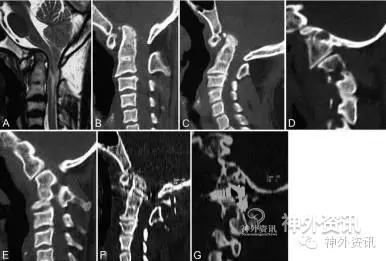

以下列举几个病例(图1、2、3、4):

图1. 21岁女性患者影像学资料。A. MRIT2加权像显示颅底凹陷症、脊髓空洞症合并Chiari畸形;B. 头部前屈位CT扫描提示,颅底凹陷症、寰椎和C2-C3融合;C. 头部仰伸位CT示,颅底凹陷症轻度减轻;D. 关节断层CT显示,Ⅱ型寰枢关节后脱位;E. 术后CT结果,颅底凹陷减轻;F. 术后关节突关节断层CT显示,颅底凹陷减轻;G. 术后X线片示植入物。